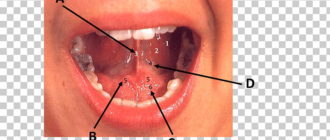

Воспалился подъязычный сосок и железа

Воспаление под языком: причины и тактика лечения Язык – один из важнейших органов человеческого